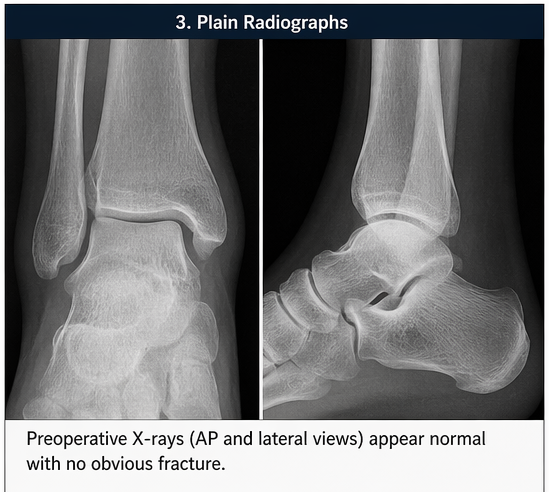

Plain Radiography:

Osteochondral fractures of the talus, often referred to as osteochondral lesions of the talus (OLT), involve injury to both the cartilage and the underlying subchondral bone of the talar dome. These injuries are frequently overlooked in the acute setting, particularly when initial radiographs appear normal.

Based on clinical findings and MRI imaging, a diagnosis of osteochondral fracture of the lateral talar dome was established.